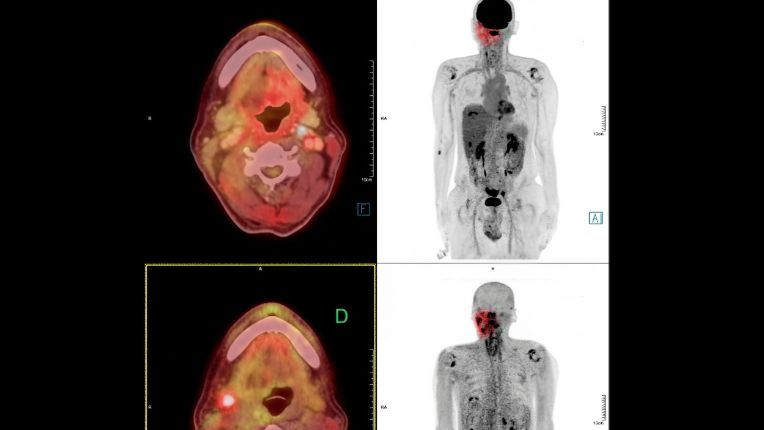

Le cancer du nasopharynx est un cancer des voies aérodigestives supérieures (VADS). Il s'agit d'une pathologie considérée comme peu fréquente. Les traitements proposés en première intention sont souvent la radiothérapie et la chimiothérapie.